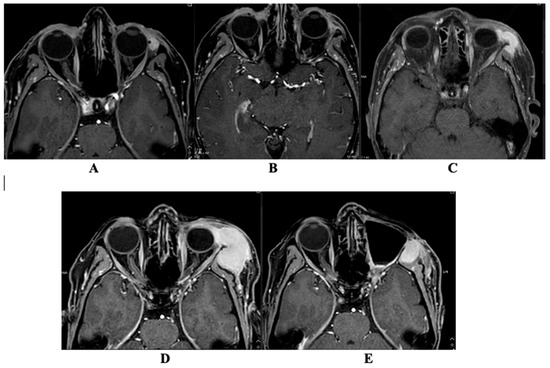

The Complexities of Periorbital Neurofibroma: Diagnostic Ambiguity and Therapeutic Dilemmas: A Case Report and Literature Review

by Marijus Leketas, Gerda Kilinskaitė, Nida Kilinskaitė, Goda Miniauskienė, Žygimantas Petronis and Audra Janovskienė

Diagnostics 2026, 16(5), 732; https://doi.org/10.3390/diagnostics16050732 - 1 Mar 2026

Background: Periorbital tumors represent a diagnostic challenge due to overlapping clinical and histopathological features. Case presentation: We present the case of a 57-year-old female with a recurrent left lower eyelid lesion initially diagnosed as malignant melanoma. Over a seven-year course, the patient underwent [...] Read more.

Background: Periorbital tumors represent a diagnostic challenge due to overlapping clinical and histopathological features. Case presentation: We present the case of a 57-year-old female with a recurrent left lower eyelid lesion initially diagnosed as malignant melanoma. Over a seven-year course, the patient underwent multiple surgical excisions, radiotherapy, systemic therapies, and repeated imaging. Histopathological findings alternated between melanoma, neuroma, hybrid peripheral nerve sheath tumor, and ultimately neurofibroma (NF1). Immunohistochemical staining repeatedly demonstrated positivity for S100 and SOX10, with variable expression of melanocytic markers, underscoring the diagnostic ambiguity between desmoplastic melanoma and NF. Despite multiple interventions, including Pembrolizumab therapy and orbital exenteration, tumor progression persisted. This case highlights the considerable difficulty in distinguishing melanoma from neurofibroma in the periorbital region, particularly when histological and immunohistochemical profiles overlap. Conclusions: Accurate diagnosis requires a multidisciplinary approach, repeated reassessment, and awareness of rare presentations. Our report emphasizes the importance of integrating clinicopathological data and selected molecular diagnostics to optimize management of such complex cases. Full article